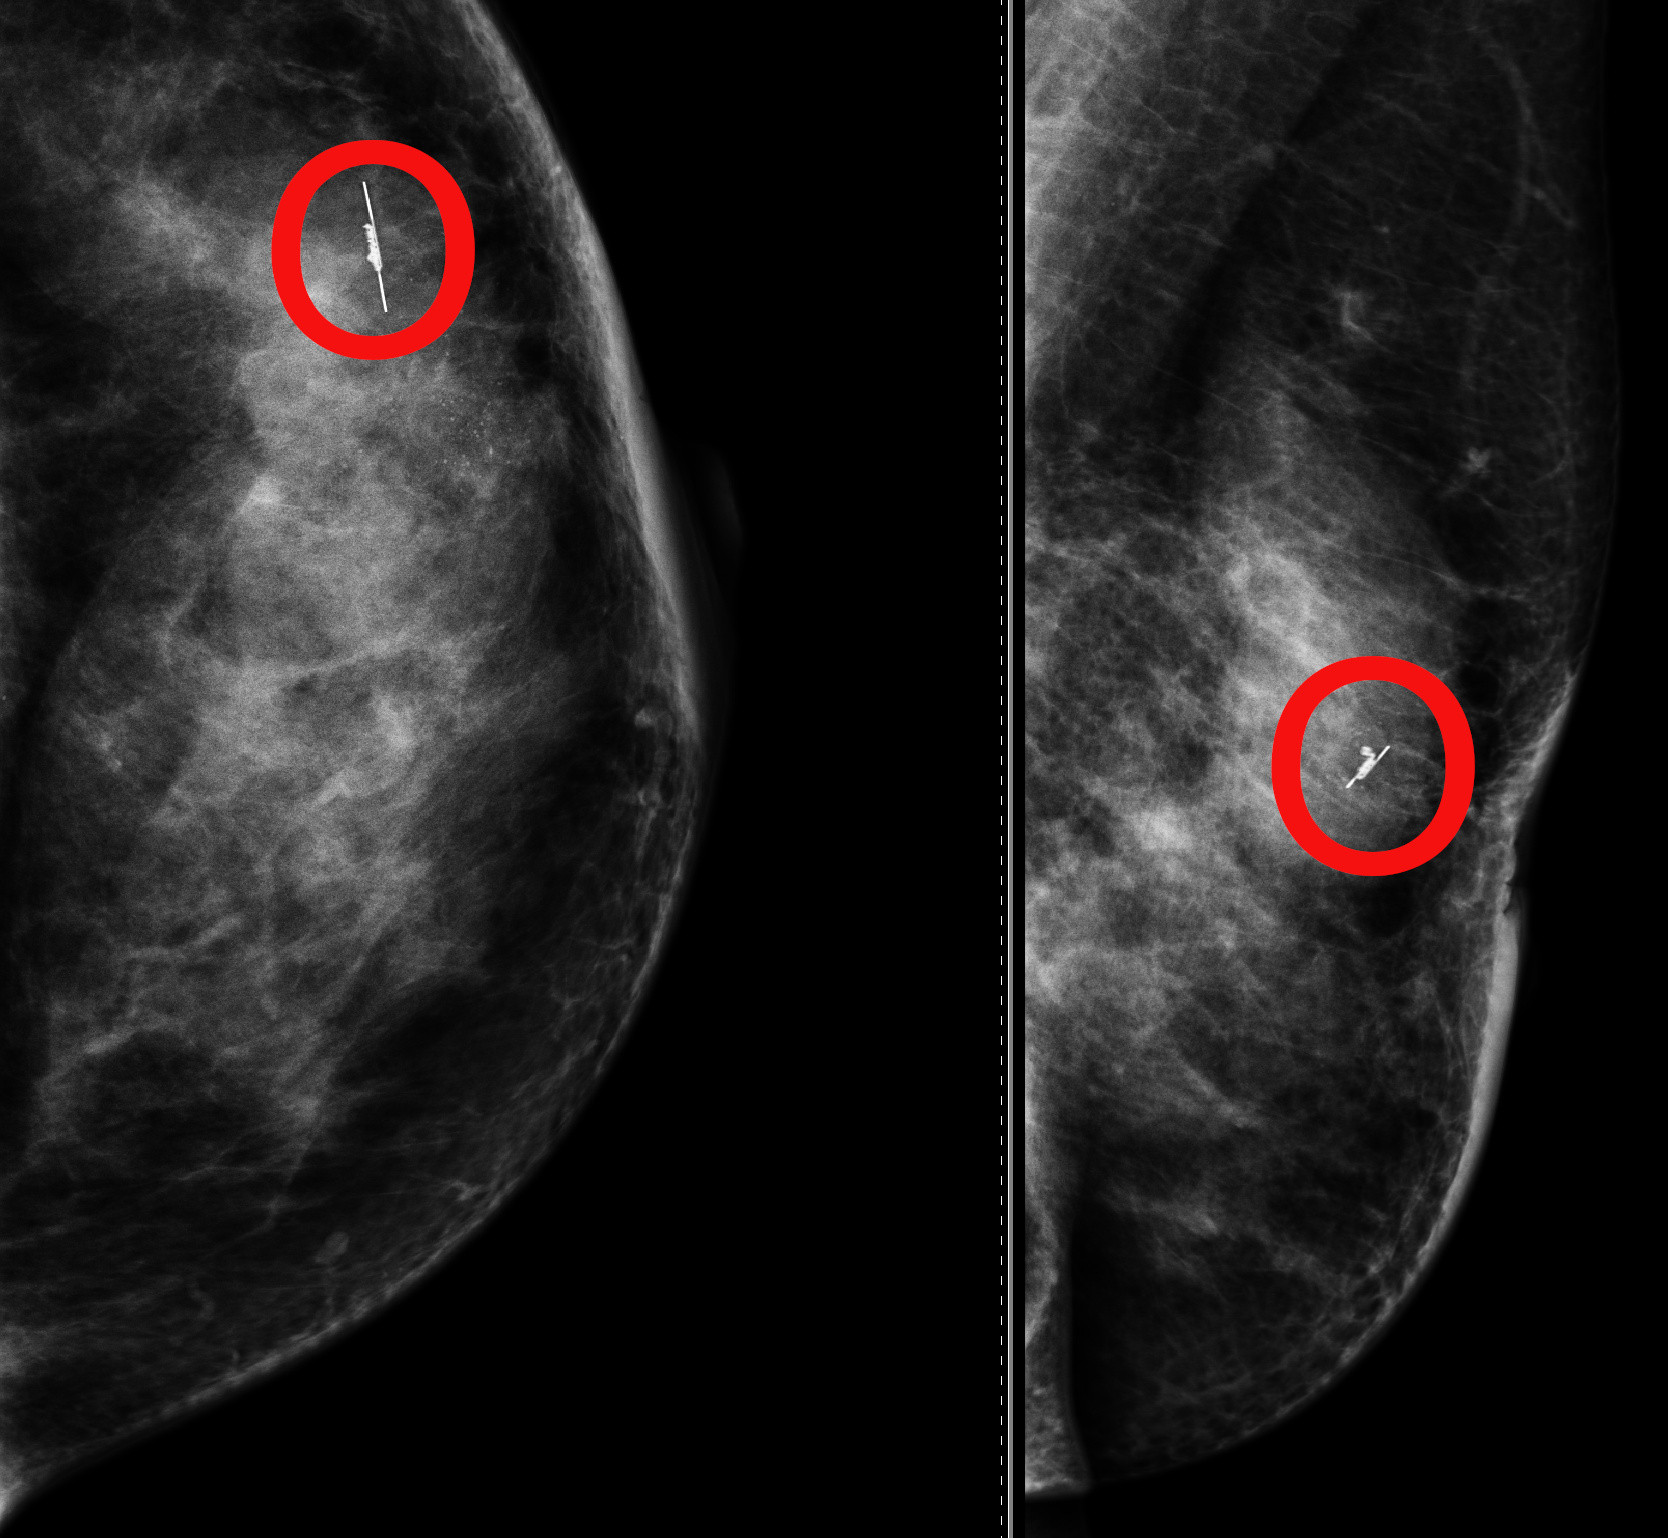

Una sorta di “mini-gps”, impiantato nella sede del nodulo mammario, che guida il chirurgo nell’individuare e asportare lesioni tumorali impalpabili: è l’innovativa metodica introdotta, per la prima volta nel Sud Italia, dall’Unità Operativa Complessa di Senologia dell’Azienda Ospedaliera Cannizzaro, centro hub nella rete regionale delle Breast Unit.

Si tratta di un dispositivo radar utile a individuare in sala operatoria la sede del tumore quando è di dimensioni molto ridotte e quindi non percettibile alla palpazione, ma visibile solo attraverso l’imaging e cioè con mammografia o ecografia.

La procedura, già utilizzata alcuni giorni fa sulle prime pazienti, prevede che, durante la biopsia del nodulo sospetto all’imaging, dalla stessa breccia dell’ago da biopsia possa essere introdotto il radar, riducendo così anche gli spostamenti delle pazienti che dunque si recheranno in Ospedale una volta sola per biopsia e identificazione della lesione. Lo stesso può essere applicato nei linfonodi che all’ecografia sono suggestivi per localizzazione metastatica.

Il radar, che si aggiunge a un’altra simile metodica in uso già da un paio d’anni apportando nuove possibilità, emette onde elettromagnetiche non radioattive a infrarossi (IR), funziona con una console che fornisce un feedback uditivo e visivo in tempo reale e viene poi rimosso in sala operatoria insieme al nodulo. Ha già dimostrato la sua efficacia sulle prime pazienti, inviate alla chemioterapia preoperatoria al cui intervento l’équipe chirurgica potrà avvalersi del dispositivo “gps”.